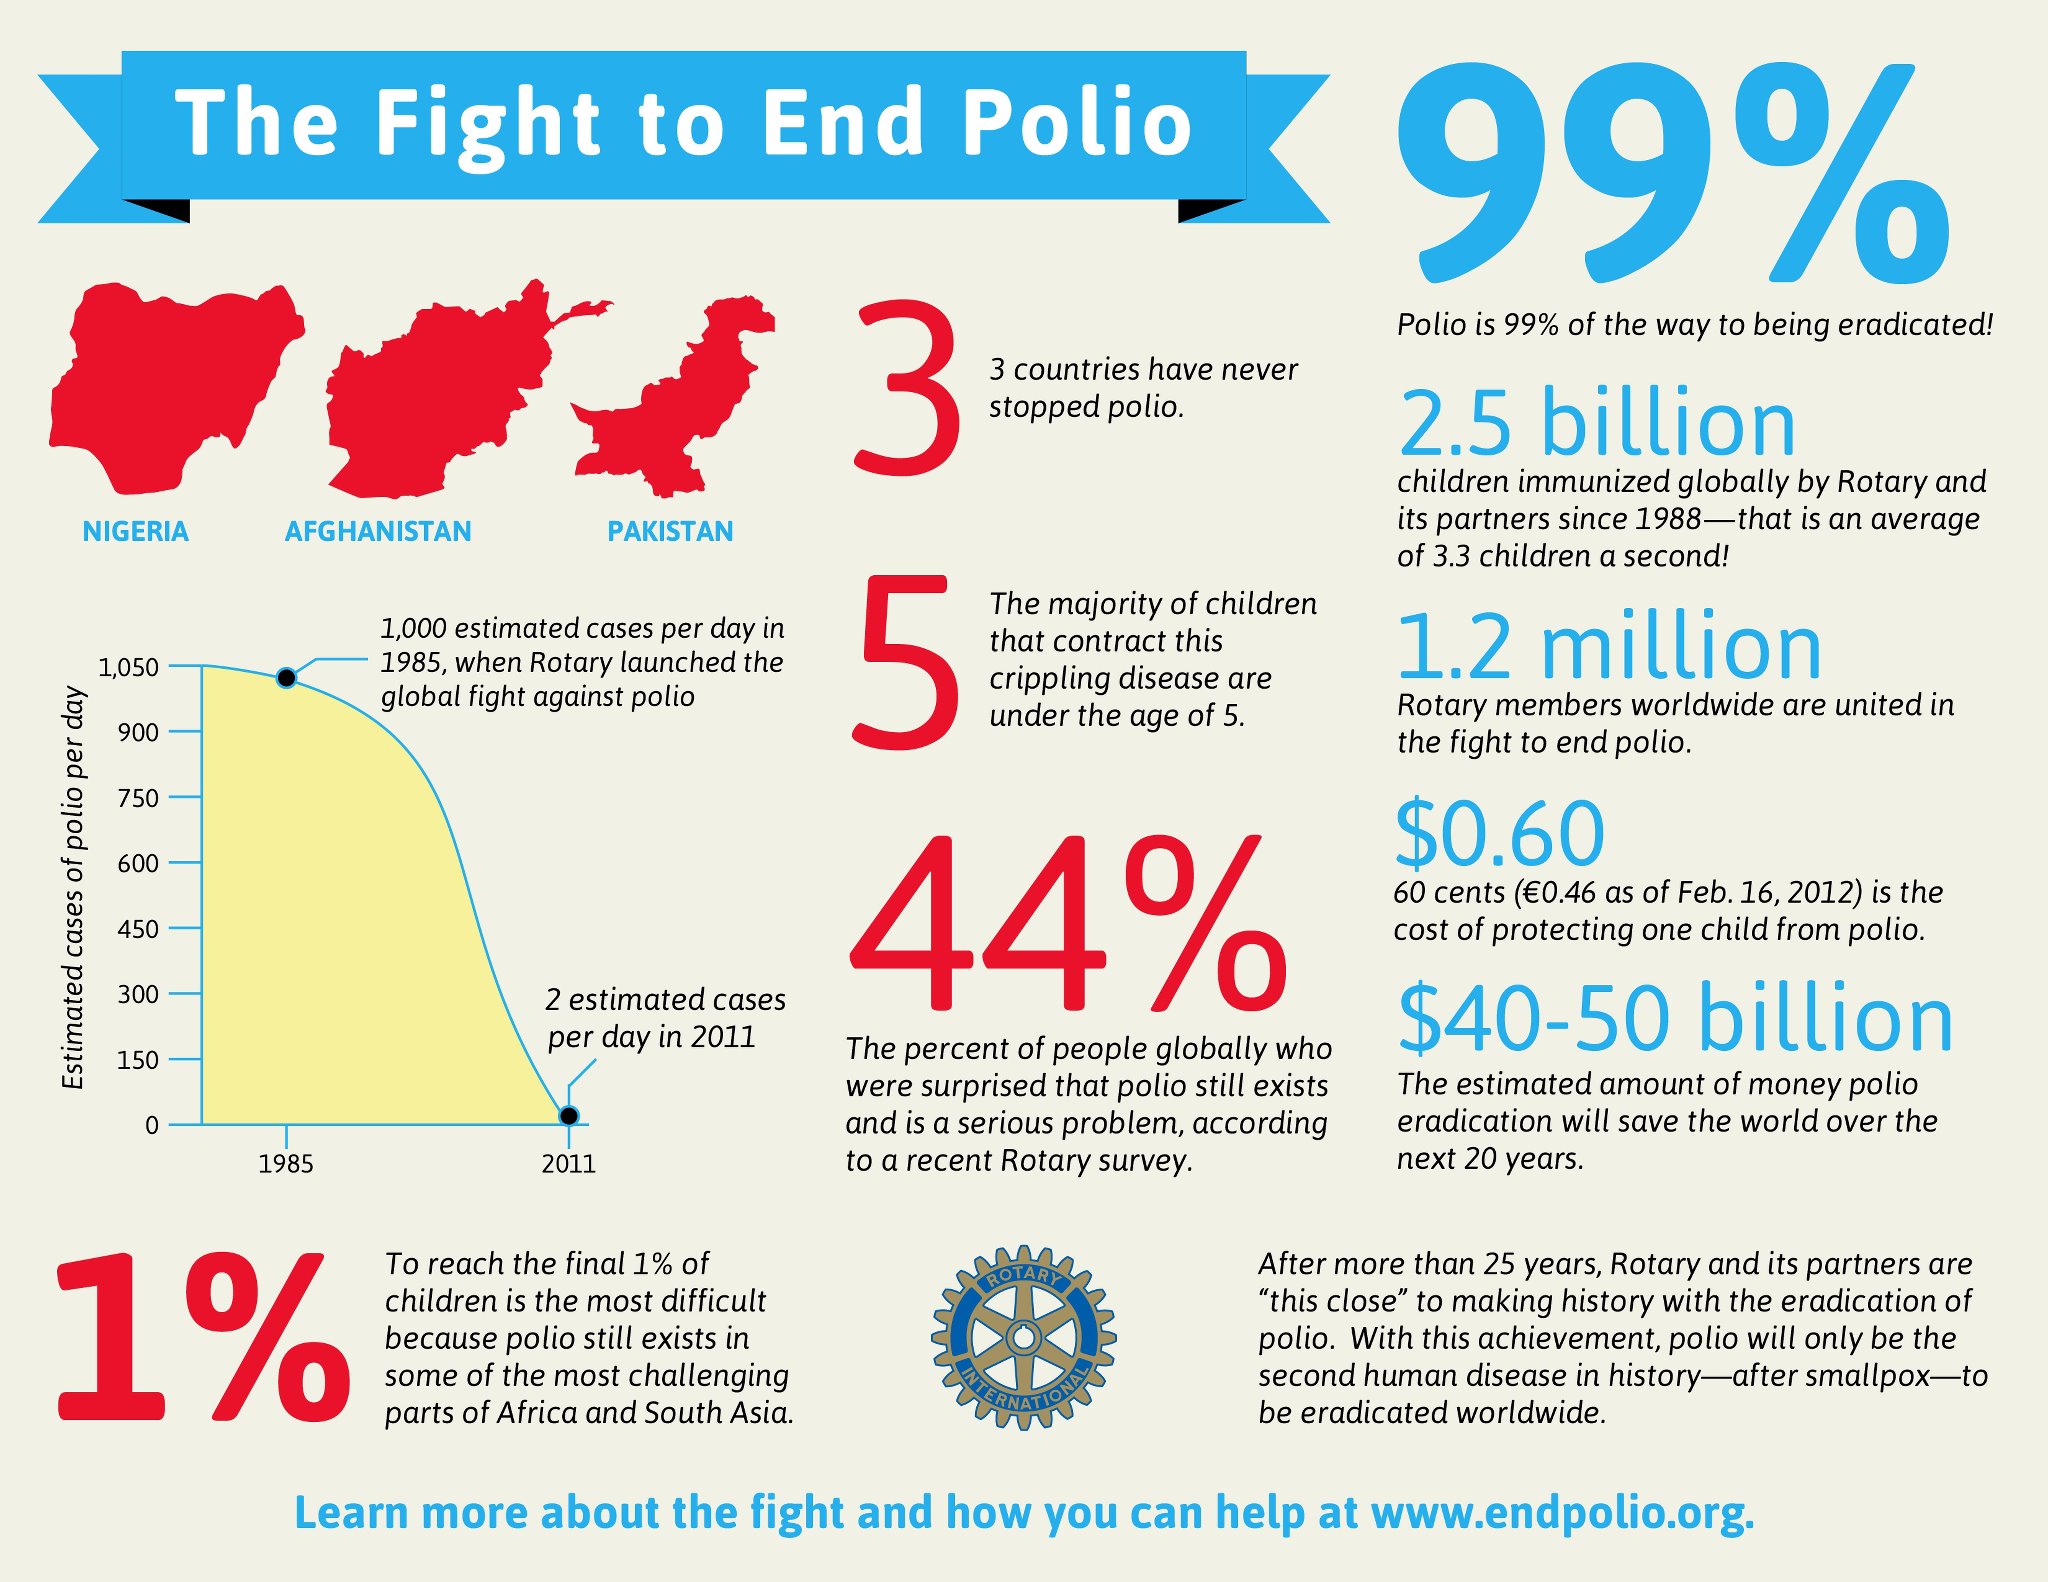

Polio:

Virus, from infected food or water

Virus, from infected food or water- Symptoms: fever, headache, vomiting, stiffness

- Complications: 1% of infected develop muscle weakness in legs, neck, head or diaphragm, meningitis (infection of spinal cord and/or brain)

- Deaths/Statistics: 2-10% of those with paralysis die from suffocation because of diaphragm muscle paralysis, making them unable to breathe.

- Thanks to vaccines, polio cases dropped from 350,000 in 1988 down to on 416 cases in 2013, spreading in the countries of Afghanistan, Nigeria and Pakistan.

- There is no cure for polio, it can only be prevented.

- It mainly affects children under 5 years of age.